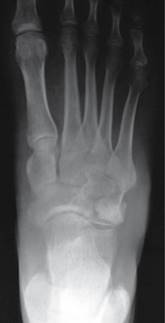

Mostró buena evolución postquirúrgica clínica y radiográfica (Figuras 6 y 7). A los tres años del procedimiento quirúrgico se encuentra sin datos de actividad tumoral local o a distancia, tolerando la deambulación sin auxiliares de la marcha y asintomático.

Figura 6: Radiografía dorsoplantal de control.